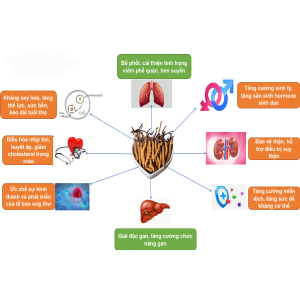

Không phải ngẫu nhiên mà đông trùng hạ thảo được coi là “vàng của Himalaya” nhờ những công dụng tuyệt vời của nó. Thật vậy, sau đây là một số công dụng của đông trùng hạ thảo, đặc biệt là đối với phái mạnh:

Tăng cường hệ miễn dịch

Đông trùng hạ thảo rất tốt cho việc củng cố hệ miễn dịch thông qua cơ chế kích thích cơ thể tiết ra nhiều chiến binh bạch cầu hơn. Nhờ chức năng này mà sức đề kháng của cơ thể trở nên mạnh mẽ hơn, chống lại những tác nhân có hại nhất là những người có nguy cơ cao bị bệnh viêm gan B hoặc bị nhiễm HIV/AIDS.

Nam giới thường có thói quen uống nhiều bia rượu và đây cũng là nguyên nhân dẫn tới tỷ lệ cao nam giới mắc những bệnh lý về gan mật. Nếu dùng đông trùng hạ thảo đúng cách sẽ giúp thải độc gan cũng như tăng cường chức năng gan hiệu quả. Cụ thể:

Trong đông trùng hạ thảo có chứa hợp chất polysaccharides và cordycepin có khả năng thúc đẩy quá trình thải độc ở gan, hạn chế sự phát triển của các bệnh về gan như nóng gan, suy gan, gan nhiễm mỡ;

Sử dụng đông trùng hạ thảo để bồi bổ cho những người bị xơ gan cũng cho ra kết quả xét nghiệm chức năng gan được cải thiện.

Sinh lý là một vấn đề rất quan trọng trong đời sống tình dục của các quý ông. Do đó mà có nhiều người, đặc biệt là đàn ông từ 35 tuổi trở lên đã tìm đến đông trùng hạ thảo như một loại thần dược giúp tăng cường chức năng sinh lý.

- Kích thích tăng tiết hormone sinh dục ở nam giới, hỗ trợ làm lưu thông khí huyết, từ đó kéo dài thời gian “lâm trận" của đấng mày râu. Nhờ vậy mà các cặp đôi đều cảm thấy thăng hoa, thỏa mãn hơn sau mỗi cuộc vui;

- Gia tăng số lượng và củng cố chất lượng tinh trùng;

- Tăng cường chức năng thận, cải thiện các triệu chứng khó chịu như nhức mỏi, đau lưng, mỏi gối, tiểu rắt và hỗ trợ trong việc điều trị một số bệnh như thận hư, thận yếu,...;

- Đông trùng hạ thảo còn hay được thêm vào các bài thuốc điều trị tình trạng liệt dương, di tinh, xuất tinh sớm nhờ công dụng ích khí, tráng dương và sinh tinh mà loại dược liệu này sở hữu;

Cải thiện chức năng hệ hô hấp

- Giảm thiểu triệu chứng của các cơn hen, bổ phổi, ít phế, giảm đau ngực, thuyên tắc phổi, viêm phổi;

- Loại trừ 2 loại vi khuẩn nguy hiểm gây bệnh viêm phổi là Tuberculosis và Mycobacterium nhờ tác dụng của hoạt chất Cordycepin;

- Kích thích sản xuất nhiều hormone Adrenalin hơn. Đây là một loại hormone có chức năng vận chuyển oxy tới não bộ và nhiều cơ quan khác trong cơ thể.

Kéo dài tuổi xuân

- Loại dược liệu này có chứa một hợp chất quý hiếm tên là selen, hoạt động tương tự như một loại chất chống oxy hóa hiệu quả giúp cải thiện vẻ đẹp của mái tóc, làn da và độ săn chắc của cơ bắp;

- Vitamin A, B, C, E và 28 loại axit béo bão hòa, không bão hòa có trong đông trùng hạ thảo cũng có khả năng ngăn chặn tuổi già ập tới quá nhanh.

Tốt cho tim mạch

Nhịp tim và quá trình lưu thông khí huyết được ổn định hơn nhờ hoạt chất D-mannitol chứa trong đông trùng hạ thảo;

Bệnh nhân đái tháo đường nên sử dụng đông trùng hạ thảo vì công dụng giảm cholesterol máu và hạ đường huyết.